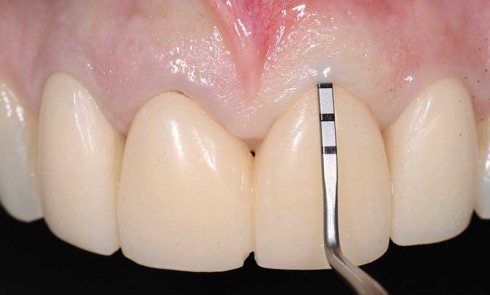

Le protocole de traitement proposé utilise le Digital Smile Design (DSD) tel qu’il a été défini par Coachman et coll....